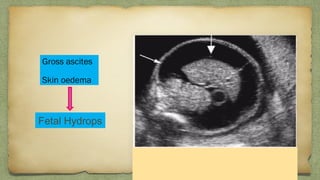

Gross ascites

Skin oedema

Fetal Hydrops